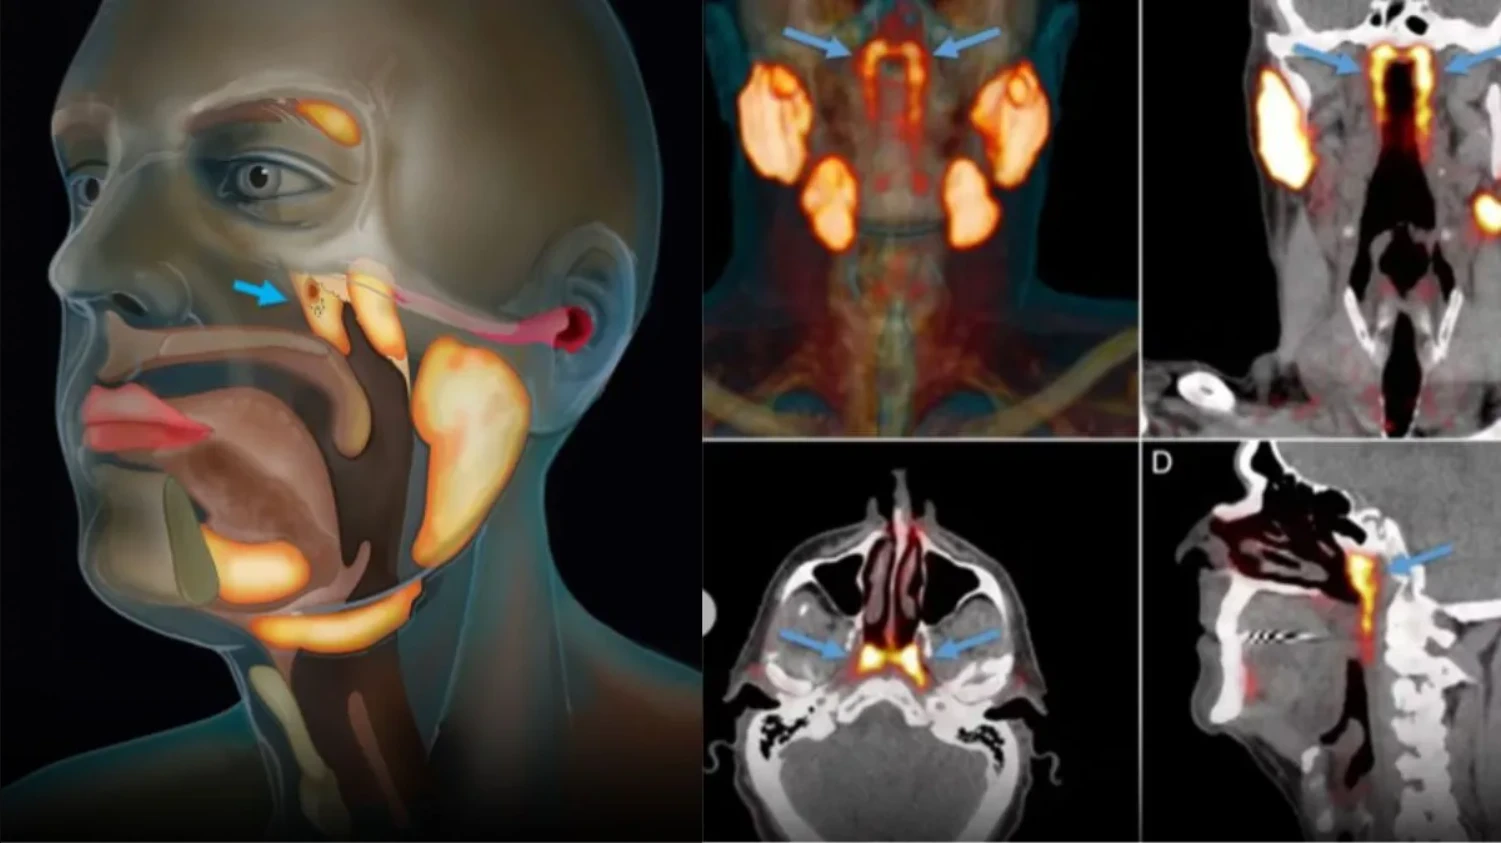

Theo PubMed, vào năm 2020, các nhà nghiên cứu Hà Lan công bố phát hiện một cặp tuyến nước bọt mới nằm ngay phía sau mũi, trong khu vực nối giữa khoang mũi và họng. Sau đó, nó đã được các chuyên gia đặt tên là tuyến nước bọt ống hầu (tubarial salivary glands). Phát hiện này lập tức làm dậy sóng truyền thông và cộng đồng khoa học vì nếu đúng, nó sẽ bổ sung vào “bản đồ” giải phẫu người vốn tự hào có 3 cặp tuyến nước bọt lớn đã được biết đến lâu nay.

Theo NKI, câu chuyện bắt đầu không phải từ phòng mổ giải phẫu mà từ… máy PET/CT cho bệnh nhân ung thư tiền liệt tuyến. Khi các bác sĩ tiêm chất đánh dấu và soi hình ảnh, họ thấy hai vùng sáng bất thường ở vòm họng xuất hiện nhất quán trong hàng loạt bệnh nhân đã gợi ý có một cấu trúc tuyến lớn hơn những “tuyến nhỏ rải rác” mà sách y đã mô tả trước đó. Khám nghiệm thêm trên xác và phân tích mô cho thấy tồn tại mô tuyến với nhiều ống dẫn, đủ để các tác giả đặt vấn đề đây là một “vùng tuyến” có thể coi là cơ quan.